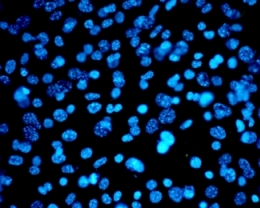

Almost $6.5 million has been awarded by the NHMRC to support a range of projects focusing on research into cancer, epilepsy, lymphedema, membrane proteins, blood cells, the role of neural crest cells in congenital malformations such as cleft palate, understanding and treating chronic pain, skin cancer, the origins of heart disease, medicine safety and Indigenous Australians experience of cancer and cancer treatment.

He says it is particularly pleasing to note the success of research from the Centre for Cancer Biology, which will be part of UniSA’s new health precinct.